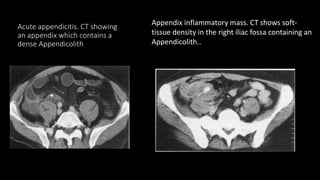

 CT findings of acute appendicitis

• 90% diagnostic accuracy to detect acute appendicitis

• Failure of appendix to fill with oral contrast

• Tubular structure 6 mm in diameter or greater with a thickened wall

• Appendicolith

• Surrounding inflammatory changes

Acute appendicitis. CT showing

an appendix which contains a

dense Appendicolith

Appendix inflammatory mass. CT shows soft-

tissue density in the right iliac fossa containing an

Appendicolith..